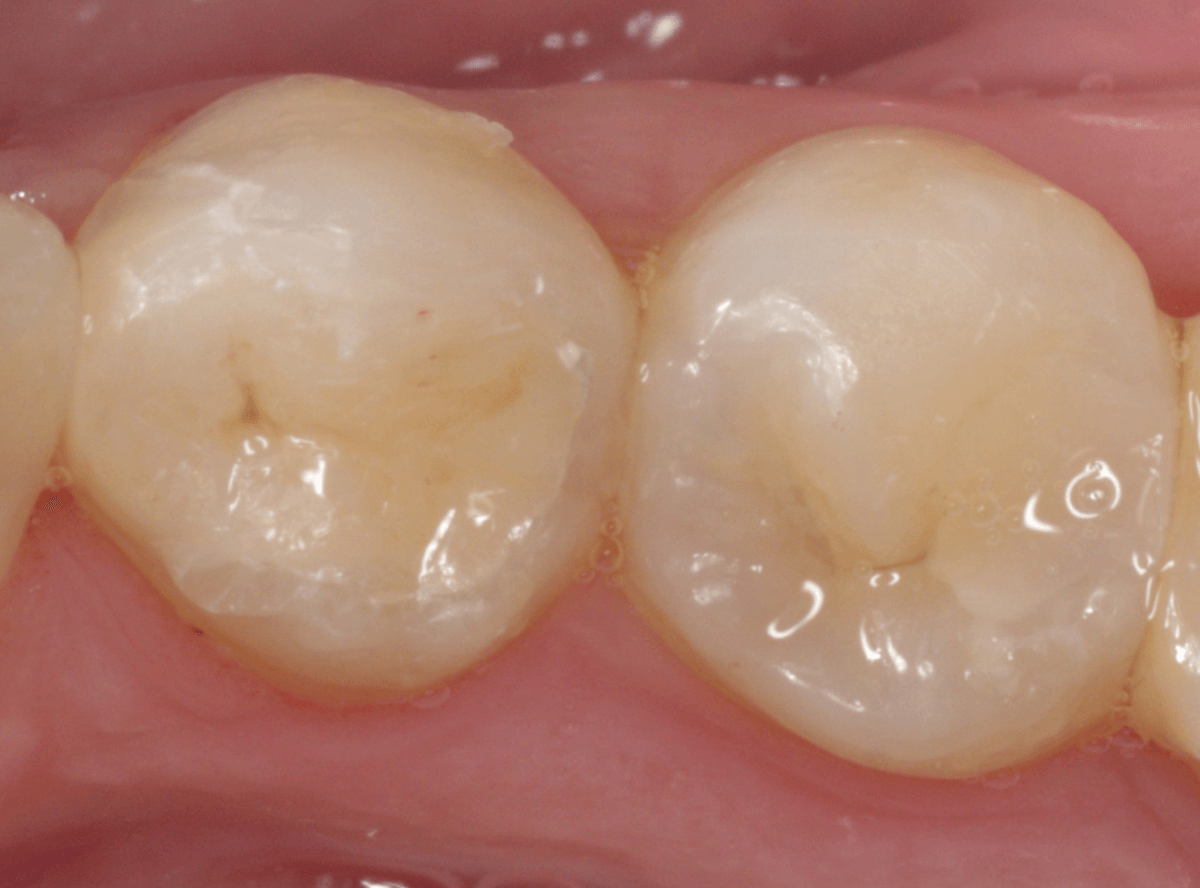

Case.22 小臼歯の広い虫歯をE-MAX・インレーで修復

虫歯の治療後にセメントをつめて経過観察していた患者さんです。

術後、特に症状もありませんでしたので、型をとってつめものをお作りするところで、セラミックでの治療をご希望されましたので、両歯ともE-MAXインレーで製作する事になりました。

型を取るために歯をトリミングします。

模型上で精密に製作します。

set後の写真です。

見た目にも違和感なく、患者さんにも満足していただけました。